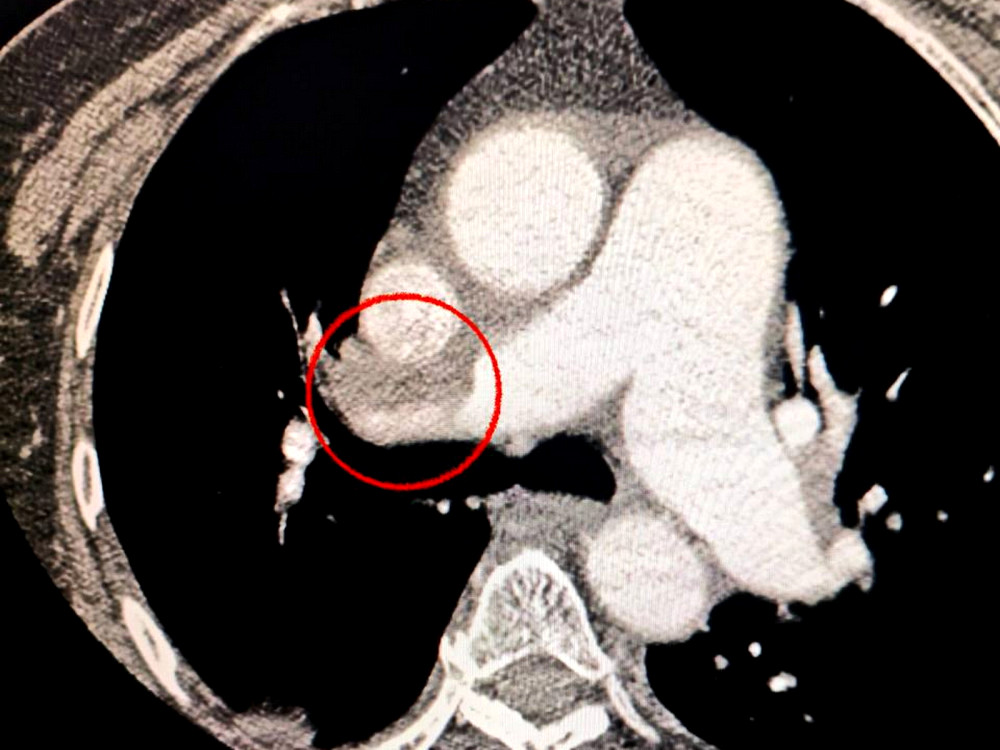

Пацієнтка, одеситка, була доставлена до лікарні з серйозним мозковим інсультом. Під час комп'ютерної томографії медики виявили тромб у середній мозковій артерії.

Лікарі також помітили, що жінка має труднощі з диханням, тому було вирішено провести додаткове обстеження легень, що підтвердило наявність тромбоемболії.